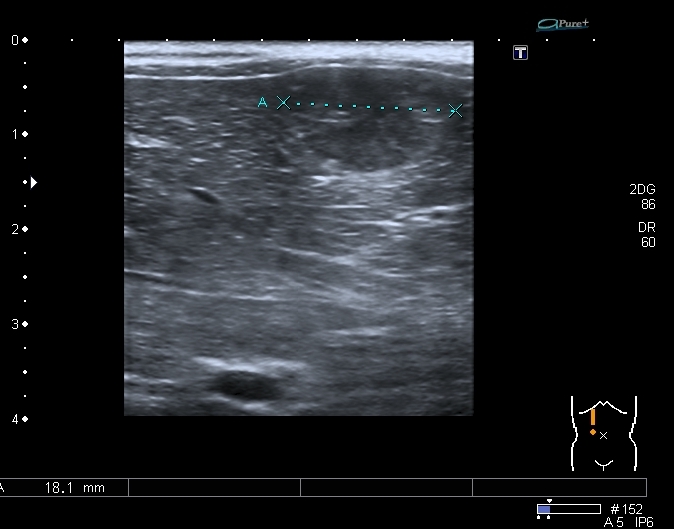

Предлагаю интересные изображения, полученные при сканировании лёгких через межрёберные промежутки и печень у ребёнка 4-х лет с подозрением на пневмонию

Согласен в отношении нижней доли правого лёгкого, изменения в ней похожи на сливную инфильтрацию при пневмонии, хотя носят несколько многоузловой характер. Но то что мы видим со спины в левом лёгком на пневмоническую инфильтрацию не похоже.

Добавляю сканы печени, я думаю они являются хорошей подсказкой о природе изменений в лёгких

Она же  с  высокочастотным датчиком субкапсулярно